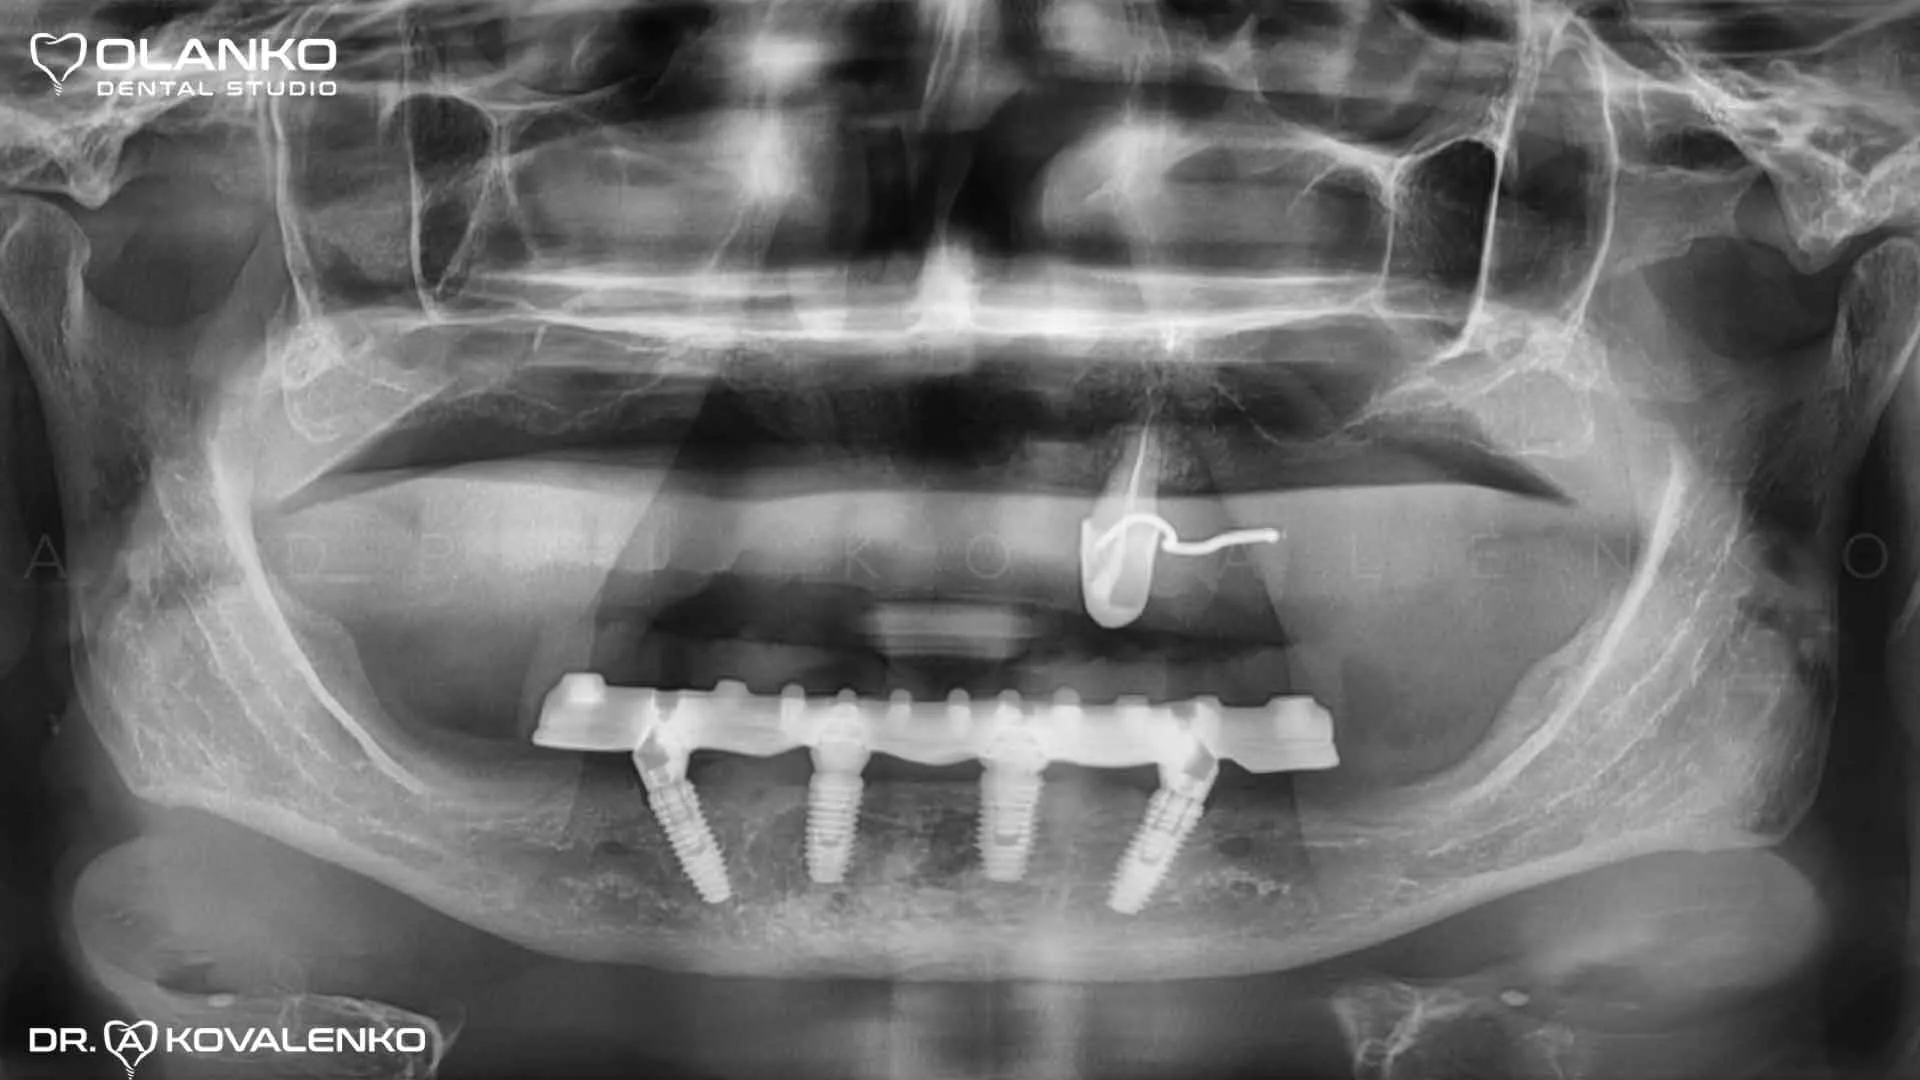

Фото панорамный рентген снимок после установки имплантов

Клинический случай 9 имплантация зубов

Контрольный рентген снимок точности установки протеза и балки